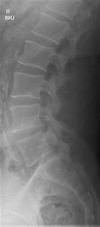

Radiographer X-ray Findings:

Findings

As requested, a spot lateral and a lateral view have been performed.

There appears to be a very minor anterolisthesis of L5 relative to S1 in the order of only 2-3mm and degenerative.

There is no other malalignment.

There is no fracture.

There is no destructive pathology.

There is good preservation of intervertebral disc heights.